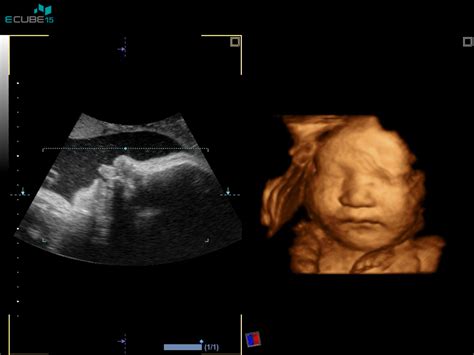

- 3D/4D ultrazvok: Omogoča bolj realističen pogled na otrokov obraz in gibanje, kar je čustveno bogata izkušnja za starše. Ti pregledi so pogosto na voljo s posnetkom na USB ključek ali CD.